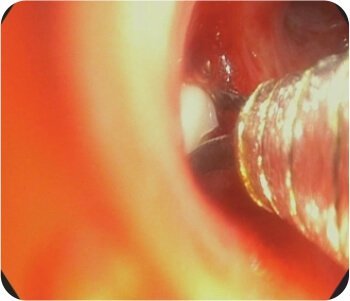

ডান উপরের লোবের অগ্রভাগের ওয়াটানাবে স্ফিগট অক্লুশন + ডান এপিকাল এবং পোস্টেরিয়র সাব সেগমেন্টের আঠালো ইনস্টিলেশন এবং ব্রঙ্কিয়াল আর্টারি এমবোলাইজেশন করা হয়েছিল।

ডান উপরের লোব ব্রঙ্কাসে আঠালো স্থাপন